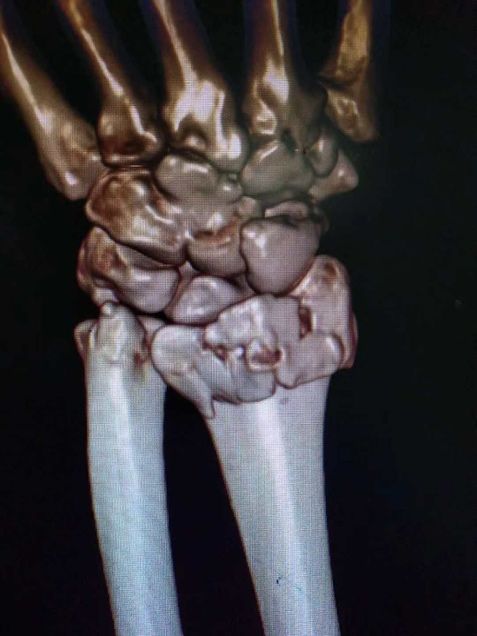

术前三维ct重建图像